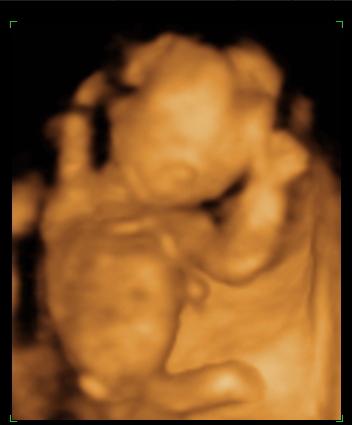

De történt jó dolog is, mert mivel ma vagyok pont 12 hetes, megnézett ultrahangon is, és minden rendben van!!!

Olyan aranyos volt, éppen aludt!

Aztán a doki megpróbálta felébreszteni, ami sikerült is. Az ébresztgetés nagy élmény volt...

Van két keze, két lába, ép gerince, és hasfala.

A BPD 21 mm,

Az NT? pedig 1,5mm(Ez mi?!)